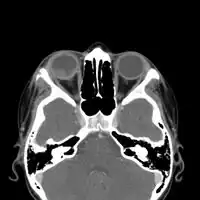

CT-scan head: Intraorbital enhancing mass lesion and two outer eyelid lesions with necrotic center and enhancing borders.

In the juvenile form, lung abnormalities are shown in high-resolution CT scans of the lungs, whereas in the chronic form plain X-rays may show interstitial and alveolar infiltrates in the central and lower lung fields.[14]